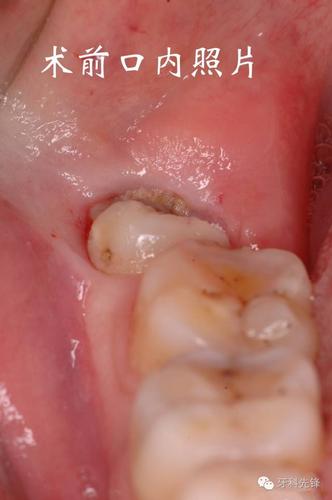

一、智齿高位近中阻生齿的特点

智齿是位于口腔后部的一组齿齿,通常在18至25岁之间开始生长。智齿的位置分为近中阻生齿和远中阻生齿,其中近中阻生齿是指智齿长在下颌骨的近中方向。

智齿的生长情况各不相同,有的智齿可以正常生长并且能够顺利地咬合到对应的上颌骨,而有的智齿则会出现生长异常,导致牙齿位置不正,甚至对周围牙齿产生影响。对于智齿高位近中阻生齿来说,由于其位置较为特殊,往往会对周围牙齿产生一定的压迫,导致口腔不适。

由于智齿高位近中阻生齿的位置较为靠近颌骨,而且与周围牙齿的位置关系较为复杂,因此其拔除难度相对较大。拔除过程中需要进行切开牙龈、骨组织切割等步骤,需要更加精细的操作技术。

智齿高位近中阻生齿的牙冠通常会部分或完全埋藏在颌骨中,这会增加拔除的难度。如果智齿牙冠部分埋藏在颌骨中,拔除时需要进行切开牙龈和骨组织的切割,才能将智齿完整地取出。